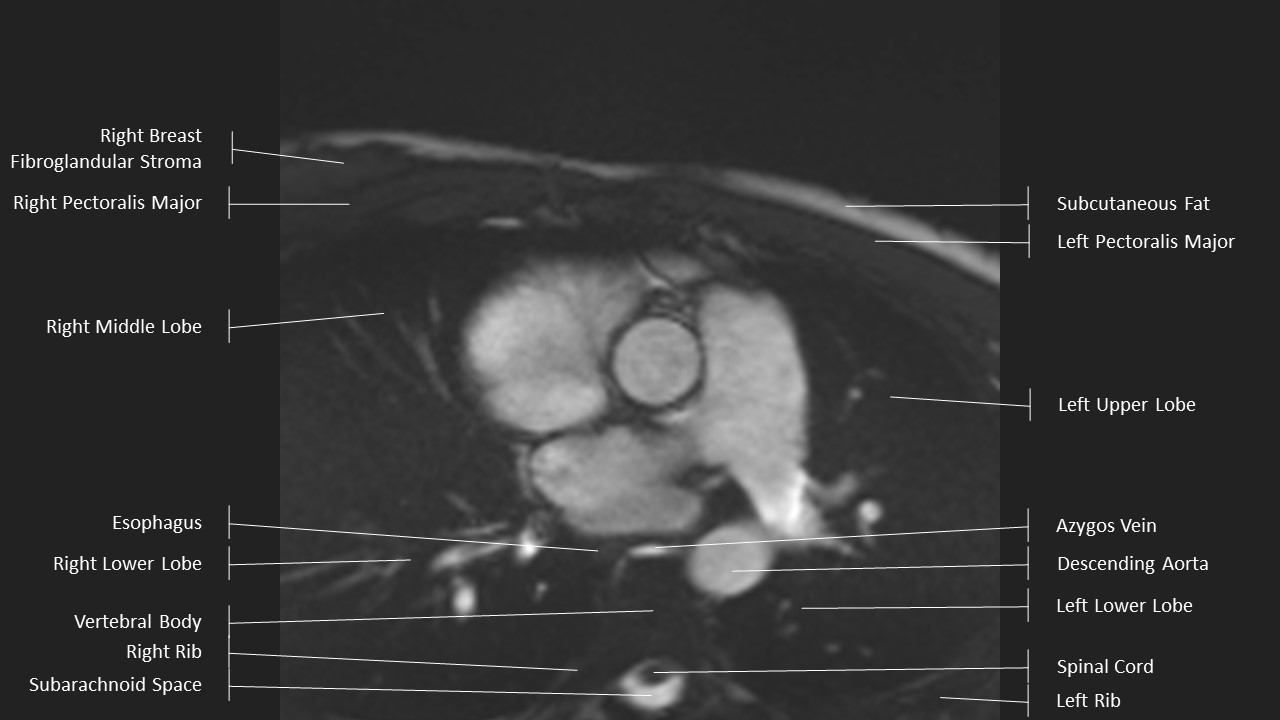

Axial Series